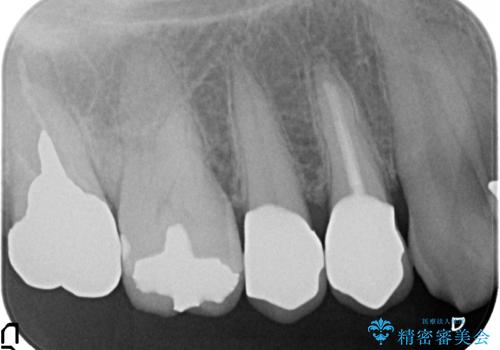

- 右上4番目の歯が黒くなっているのが気になるといらっしゃった方の症例です。

再根管治療後、オールセラミッククラウンによる補綴を行いました。

右上5も虫歯があったためオールセラミッククラウンによる補綴を行っております。

今回用いたオールセラミッククラウンはジルコニアフレームという白い素材の上にセラミックを盛っているため、審美性が非常に高いのが特徴です。

また、ジルコニアは人工ダイヤモンドの材料にも使われているほど高い強度を持っており、そのためオールセラミッククラウンは審美性だけでなく、奥歯やブリッジの補綴も可能とするクラウンです。